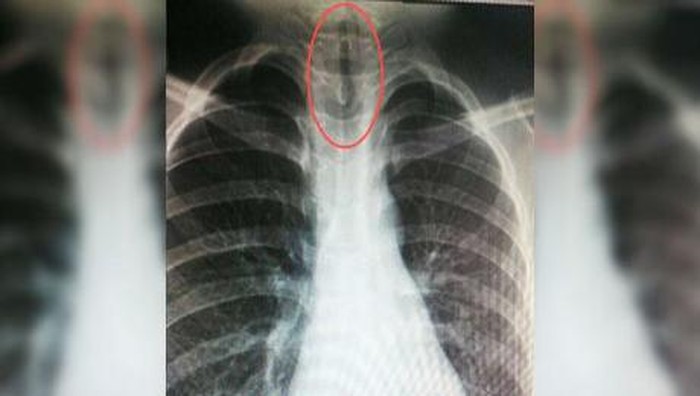

Beberapa waktu kemudian seorang pria 50 tahun asal Hongkong mendatangi Kwong Wah Hospital karena sakit perut yang tak tertahankan. Setelah diperiksa ternyata terjadi peradangan pada dinding bagian dalam perut si pasien atau peritonitis. Namun secara mengejutkan dokter melihat bayangan seekor belut di dalam perutnya dari hasil radiografi.

Setelah ditanya-tanya, barulah si pasien mengaku telah memasukkan seekor belut ke ususnya untuk meredakan sembelit. Tapi bukannya sembuh, si belut justru menggigit sebagian besar usus si pasien hingga berlubang sepanjang 3 cm. Belut sepanjang 50 cm itu kemudian dikeluarkan dan pasien diperbolehkan pulang.